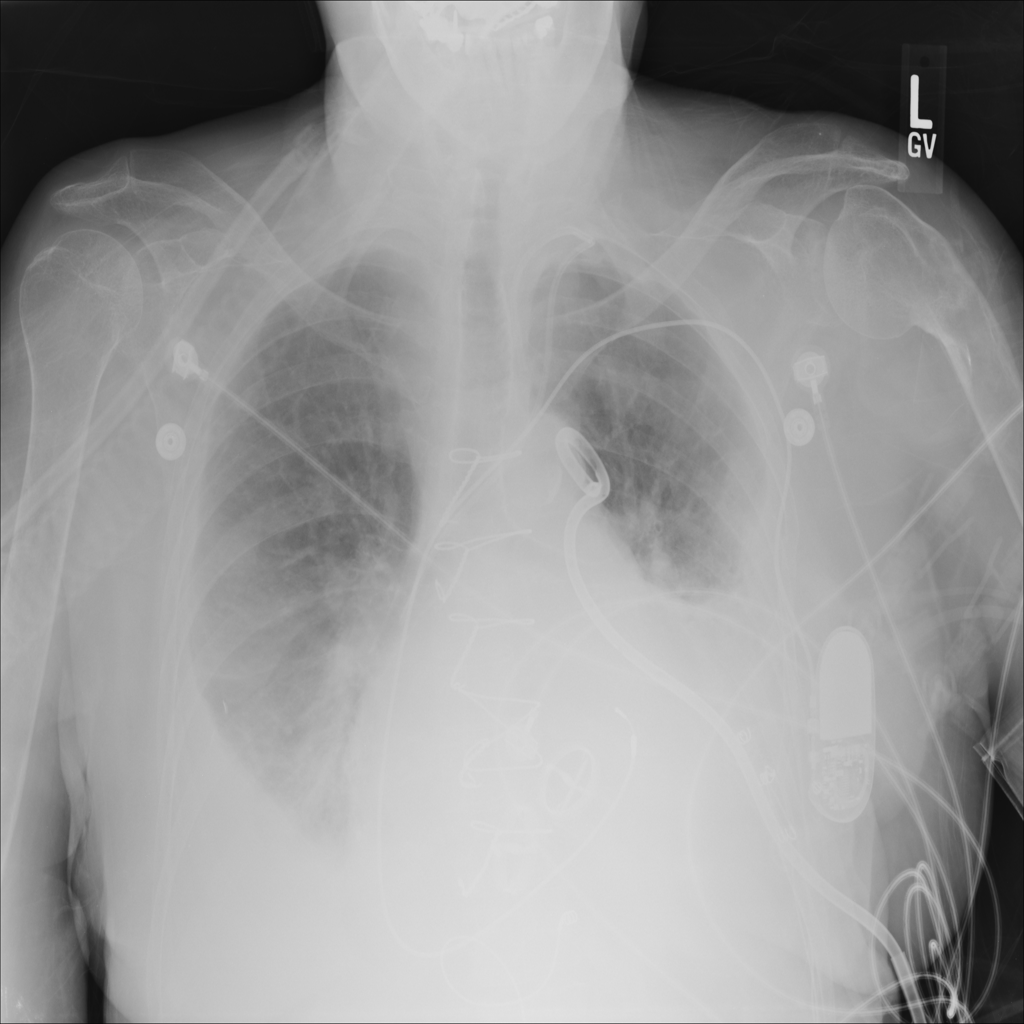

PAT-E81B · IMG-000Effusion

PAT-E81B · IMG-000

PA